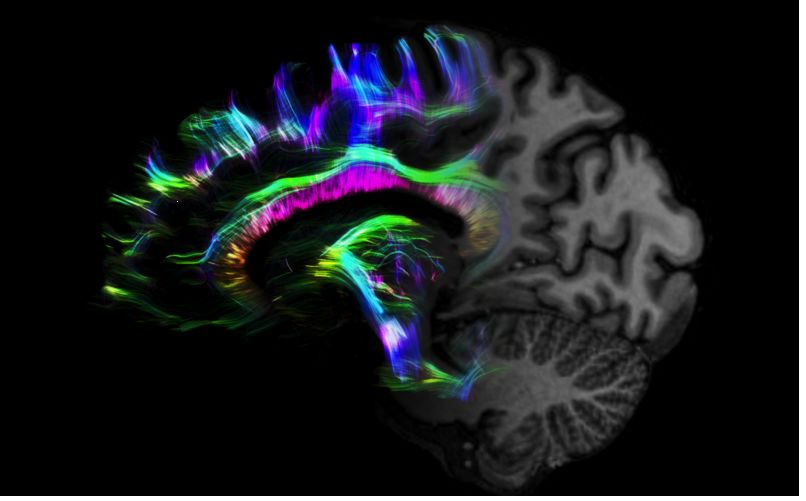

1毫米的各向同性分辨率DTI:神經(jīng)纖維束的交叉細(xì)節(jié)顯示

0.8毫米的各向同性分辨率:精確劃分灰質(zhì)和白質(zhì)

0.8毫米的各向同性分辨率:超精細(xì)的解剖細(xì)節(jié),例:小腦的精細(xì)結(jié)構(gòu)

超精細(xì)的解剖細(xì)節(jié):T2對(duì)比

0.17 x 0.17 x 0.8毫米分辨率超高。

(TOF)300微米的各向同性分辨率顯示最小的血管